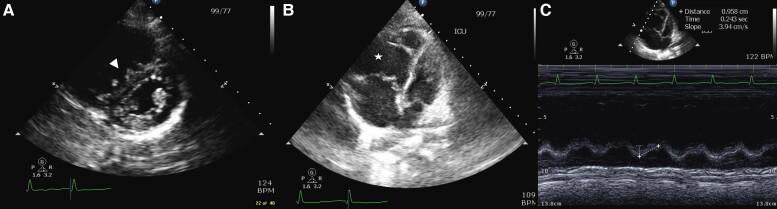

A 25-year-old female presented to the hospital with two weeks of progressive fatigue, dyspnoea, myalgias, and arthralgias. She was admitted for symptomatic anaemia requiring transfusion. Her symptoms persisted and she developed severe PH and RHF, complicated by cardiogenic shock and multiple episodes of cardiac arrest. She was found to have severe vitamin C deficiency secondary to a severely self-restricted diet. After repletion of vitamin C, the patient had complete resolution of RHF and PH.

一名25岁女性因进行性疲劳、呼吸困难、肌痛和关节痛两周前来就诊。她因症状性贫血需要输血而入院。她的症状持续存在,并发展为严重的肺动脉高压和右心衰竭,并发心源性休克和多次心脏骤停。发现她因严重的自我限制饮食继发严重维生素C缺乏。补充维生素C后,患者的右心衰竭和肺动脉高压完全缓解。